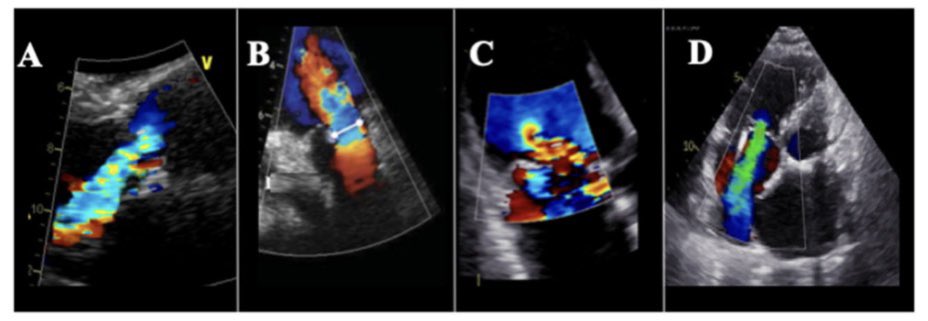

75 yo M presented late with Ant wall MI, echo suspected large contained rupture/ pseusoaneurysm confirmed on CT. Awaiting surgery @nicvd_karachi @alexsfelixecho #echofirst @iamritu @m_naeem_88 @Heart_SCCT @AJamilTajik @NicvdImaging #multimodalityimaging

SabhaBhatti's tweet image. 75 yo M presented late with Ant wall MI, echo suspected large contained rupture/ pseusoaneurysm confirmed on CT. Awaiting surgery